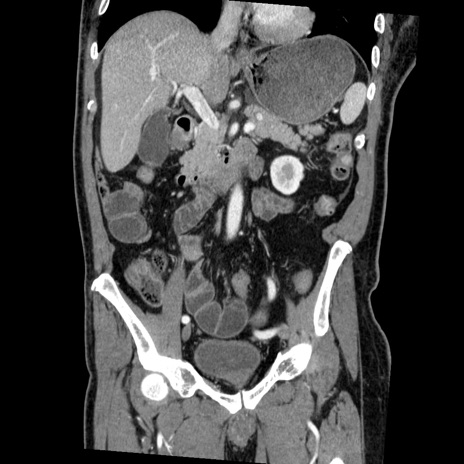

横断像

【症例】50歳代男性

【主訴】腹痛

【現病歴】AVMからの被殻出血のため回復期リハ病棟入院中。 本日午後3時頃急に下腹部痛が出現した。

【既往歴】AVM、被殻出血、虫垂炎、高血圧

【身体所見】意識晴明、左半身不全麻痺、会話の理解は良好、36.5°C、腹部:膨隆、全体に板状硬、下腹部正中に圧痛点あり、反跳痛-、筋性防御不明、右下腹部にope scar

【データ】WBC 9400、CRP 0.06